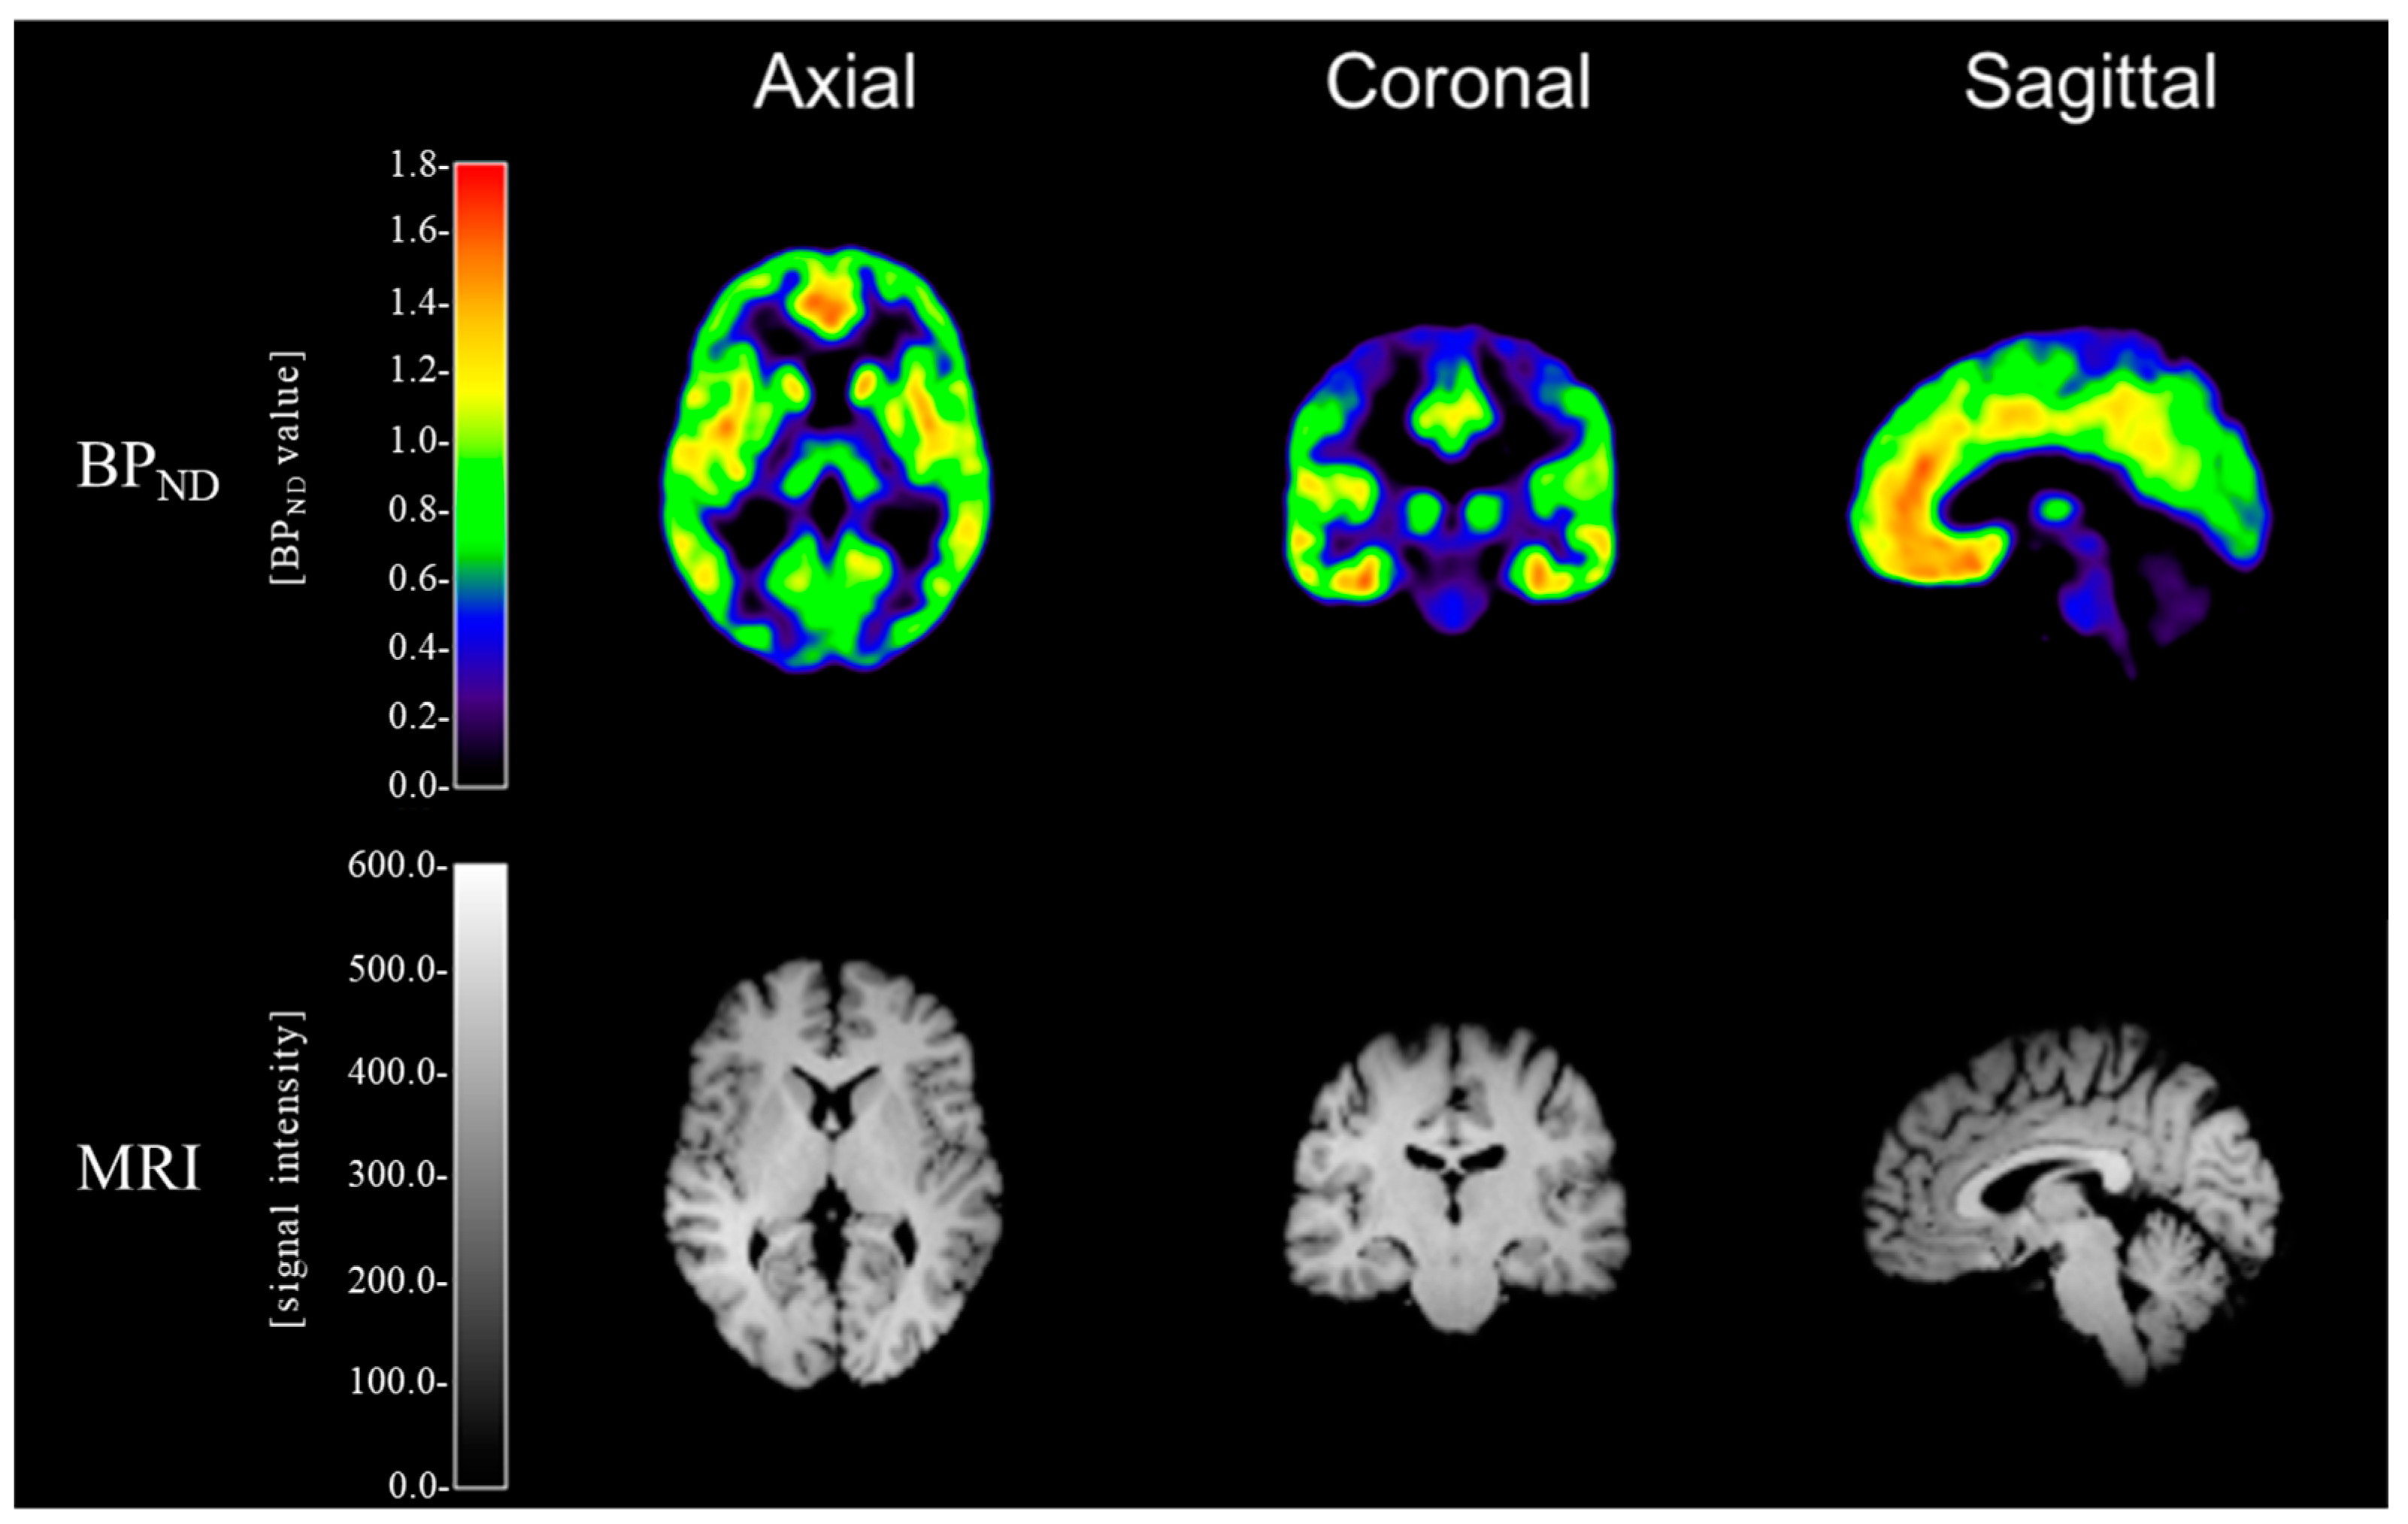

The 3D T1MPRAGE MRI images of each subject were coregistered to his PET images using statistical parameter mapping 8 (SPM8; Wellcome Trust Center for Neuroimaging, London, UK). The spatial normalization of the coregistered MRI images of each subject was performed on the Montreal Neurological Institute (MNI) template using SPM8, and the calculated transform was applied to the corresponding PET images. Time–activity curves of [11C]ABP688 PET were generated from dynamic PET images by frame-wise averaging of all voxels within each region of interest (ROI), which were coregistered to the corresponding MRI images. For the estimation of mGluR5 availability, [11C]ABP688 BPND was derived from each ROI using the simplified reference tissue model 2 (SRTM2) [38] with cerebellar gray matter as the reference region [39,40,41], based on the parameter estimation implemented in the PMOD software v3.2 (PMOD Technologies Ltd., Zürich, Switzerland). The cerebellar gray matter has been validated as a suitable reference region for [11C]ABP688 PET [42,43]. In addition, postmortem studies of mGluR5 mRNA or protein expression have reported that specific mGluR5 binding in cerebellar gray matter is negligible [44,45,46]. Moreover, in our study, there was no significant difference in cerebellar standard uptake value (SUV) between the alcohol and control groups (p = 0.45) (Supplementary Figure S1), nor was there any significant group difference in cerebellar gray matter volume (absolute volume: p = 0.92; relative volume: p = 0.76) (Supplementary Figure S1). Representative examples of [11C]ABP688 BPND and 3-Tesla MR images are shown in Figure 1. The BPND values were obtained in the 14 predefined ROIs using the automated anatomical labeling (AAL) program [47] and in the one predefined ROI using the manual mask. The manually defined mask of the ventral striatum, which is not defined on the AAL program, was drawn on the spatially normalized mean T1 MR image following previously defined divisions [48,49]. The ROIs were the anterior cingulate gyrus, superior frontal cortex, middle frontal cortex, inferior frontal cortex, superior parietal cortex, inferior parietal cortex, superior temporal cortex, middle temporal cortex, hippocampus, amygdala, thalamus, caudate, putamen, globus pallidus, and ventral striatum. These 15 ROIs were selected based on previous mGluR5 PET studies on alcohol dependence [19,23,24], and informed by literature implicating the regions as major nodes in a cortico-basal ganglia-limbic network in alcohol dependence [50].

Figure 1.

Representative examples of [11C]ABP688 BPND and 3-Tesla MR images of a control subject. (MNI coordinates: x = 3.0 mm, y = -19.5 mm, and z = 4.5 mm).